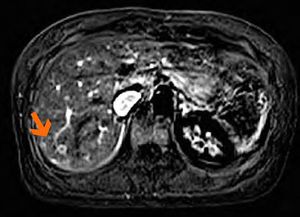

CAIPIRINHA-Dixon-TWIST (CDT) Volume-Interpolated Breath-Hold Examination (VIBE) is a new MR technique for fast Time-Resolved dynamic 3-Dimensional (3D) Imaging of the abdomen with high spatial resolution. The technique seems suitable for the detection and characterization of focal abdominal lesions such as liver and pancreatic masses. For the feature of metastasis, CDT-VIBE not only provides the ring-like enhancement pattern, but also clearly shows the feeding vessel of the lesion. Figure: Feeding vessel of the lesion is visualized in the 3D subtracted arterial phase images (Wang et al., 2014).